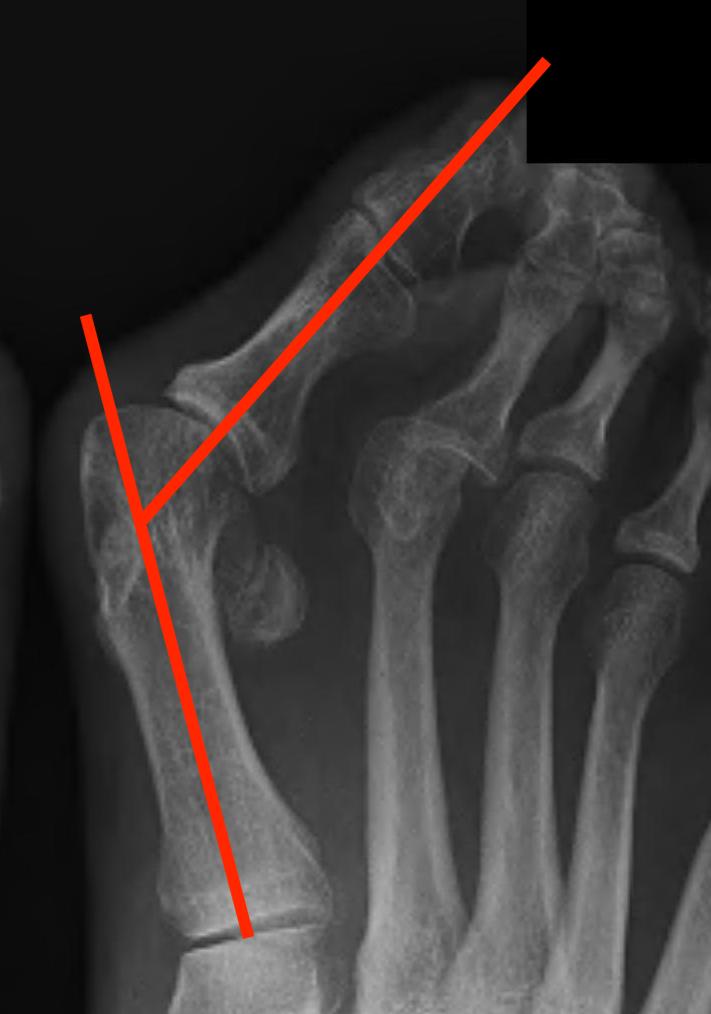

Weight Bearing AP X-ray

Angles

| HVA | DMAA | IMA | HVI |

|---|---|---|---|

|

HVA - hallux valgus angle - metatarsophalangeal angle (MTPA)

Normal < 15o |

Distal metatarsal articular angle

Intermetatarsal angle

Normal < 9o |

Hallux valgus interphalangeus

Normal <10o |